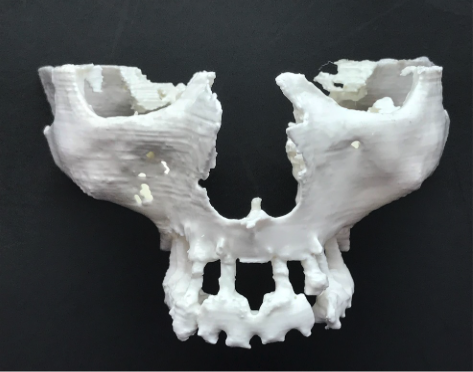

Modelos de planificación 3D para implantes zigomáticos

Modelos 3D de CBCT de esqueleto facial par la planificación de IMPLANTES ZIGOMÁTICOS.

Modelos de planificación 3D para estructuras subperiósticas

Modelos 3D de CBCT de esqueleto facial par la planificación de Estructuras Subperiósticas.

Paciente con atrofia total del maxilar, resuelta con Implantes ZIGOMÁTICOS y 1 implante anterior. Planificación informática y Modelos 3D

Paciente con atrofia maxilar total, resuelta con la colocación de 4 implantes zigomáticos. . La prótesis definitiva ha sido realizada en metal-cerámica.

Planificación informática y modelos 3D

Atrofia maxilar total, resuelta con la colocación de 2 implantes zigomáticos y 2 implantes anteriores . Planificación informática y modelos 3D.

Atrofia maxilar total, resuelta con la colocación de 2 implantes zigomáticos y 2 implantes anteriores . Planificación informática y modelos 3D.

Atrofia maxilar total, resuelta con la colocación de 4 implantes zigomáticos. Planificación informática y modelos 3D

Planificación informática y modelos 3D.